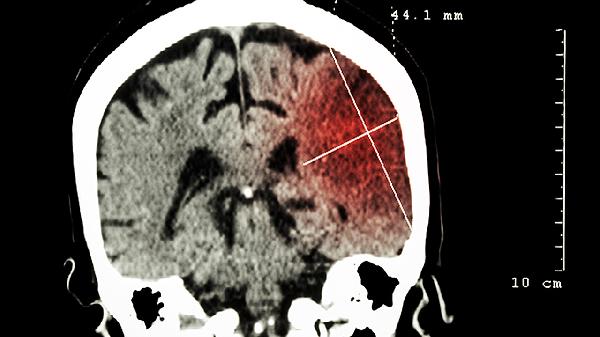

醒脑降压丸适合用于原发性高血压的辅助治疗,尤其是伴有头痛眩晕、面红耳赤、易怒等肝阳上亢表现的患者。药物中的活性成分能够帮助扩张外周血管,降低血管阻力,同时调节中枢神经系统功能,达到降压效果。长期服用可在一定程度上预防高血压引发的脑血管并发症。